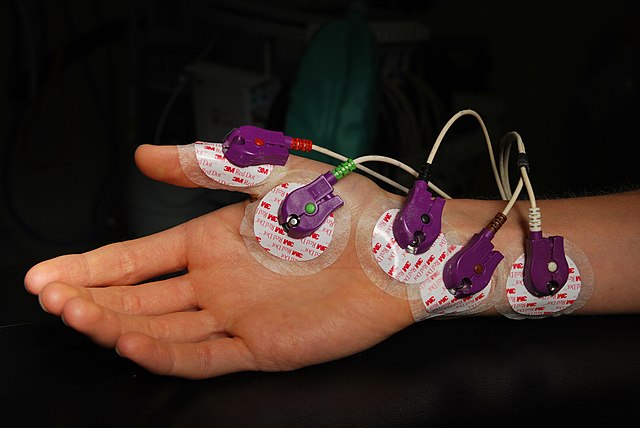

La función neurológica también debe ser evaluada para comprobar la integridad de los nervios cubital y mediano. La forma más rápida y eficiente es a través de la evaluación de los impulsos nerviosos con electromiografía. Pero también existen pruebas físicas en caso de que no se cuente con el estudio.